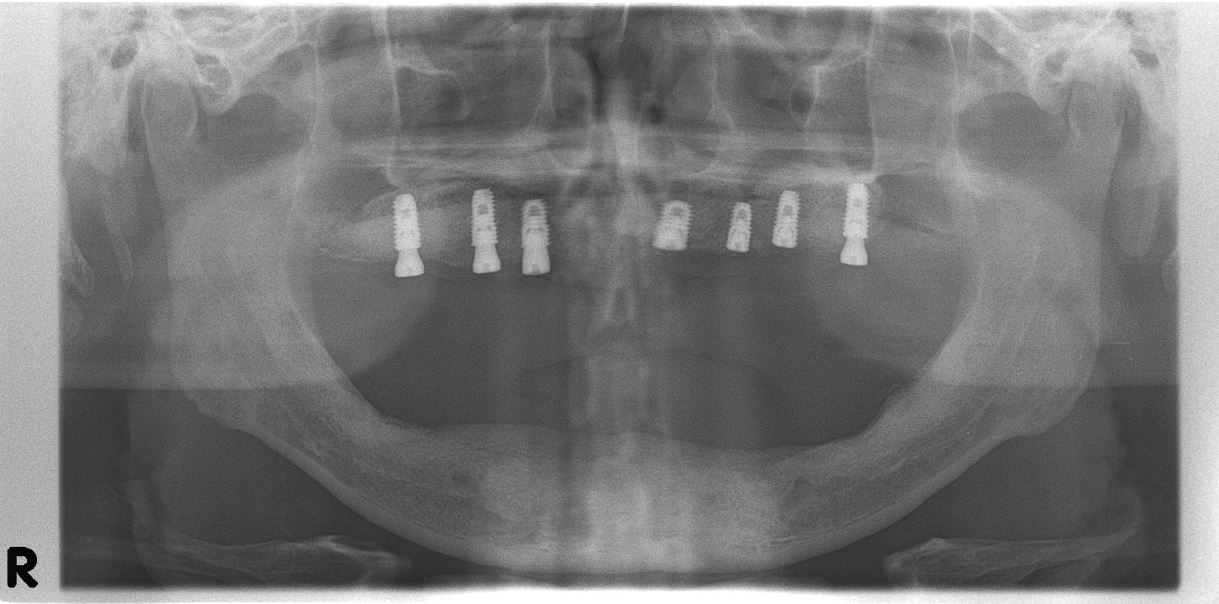

Postoperative panoramic radiography shows the precise placement of implants within the anterior and both sinus augmented areas 1 month after the surgery (Fig. 6). After the healing period, provisional denture was delivered on completely healed soft tissue and periodically adjusted to minimize the patient’s discomfort.